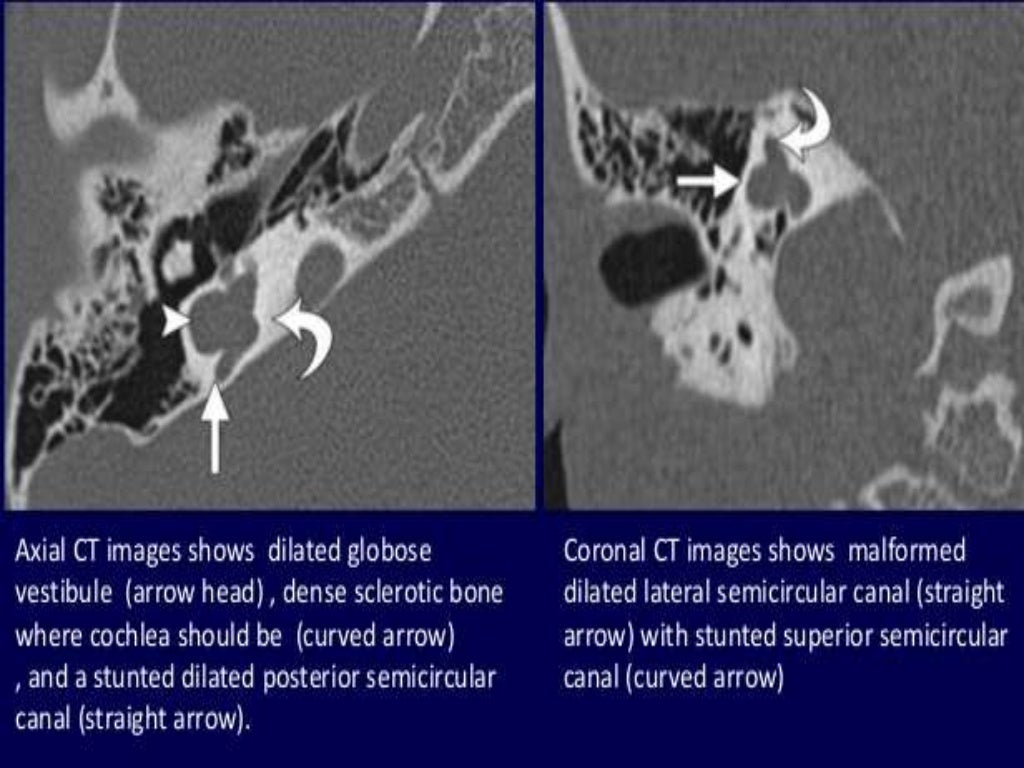

Presentation1.pptx, radiological imaging of inner ear diseases Adhesive Middle Ear Disease Radiology Adhesive otitis media is a form of chronic otitis media where there is an adhesion of medial ear structures as a result of chronic inflammation. There are a myriad of causes for this but they can be. There are often complete or. Adhesive otitis media is a severe form of chronic otitis media with atelectasis and fibrous adhesions of the. Adhesive Middle Ear Disease Radiology.